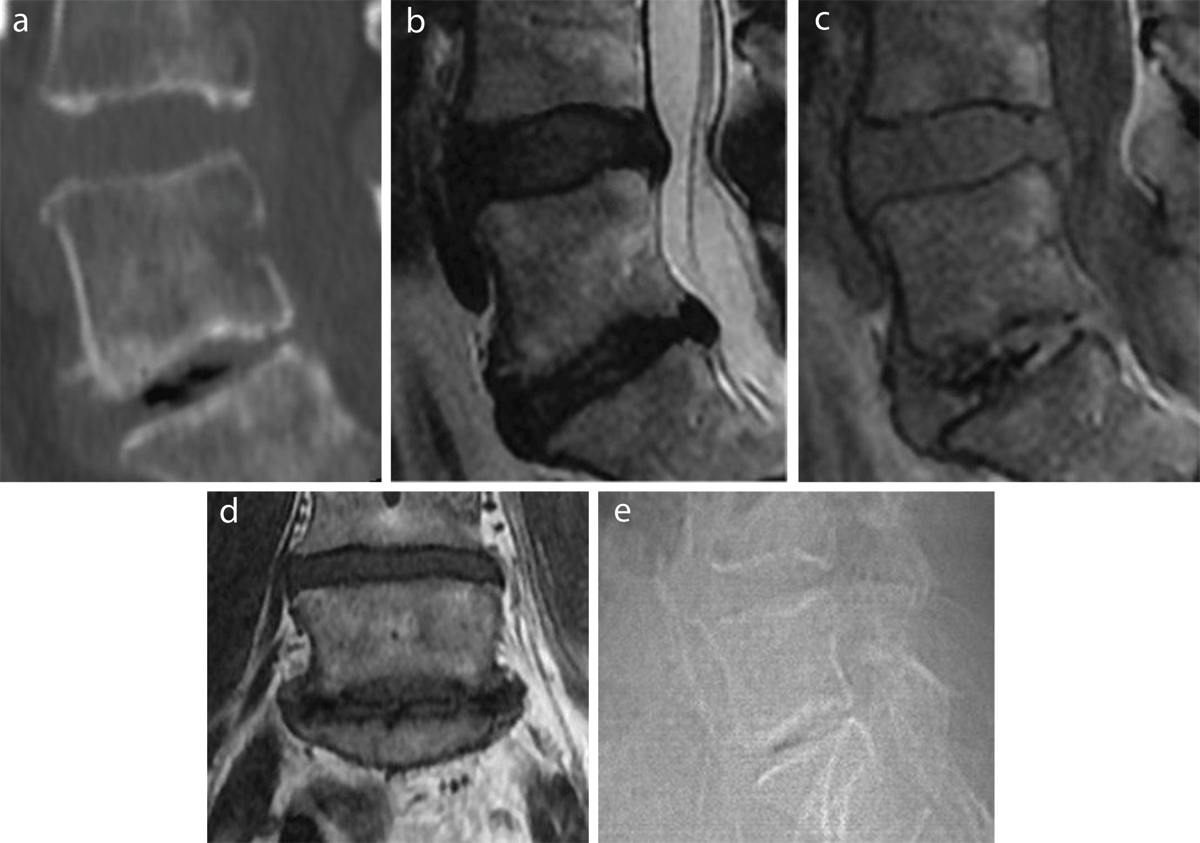

Figure 1

VP as intradiscal gas in the lower (L5-S1) of the two visualized discs (L4-L5 and L5-S1) on a sagittal reconstruction of a CT lumbar spine in bone window (a), a sagittal T2- (b) and GE-weighted image (c), a coronal T1-weighted image (d), and the lateral scout image from the CT exam (e).